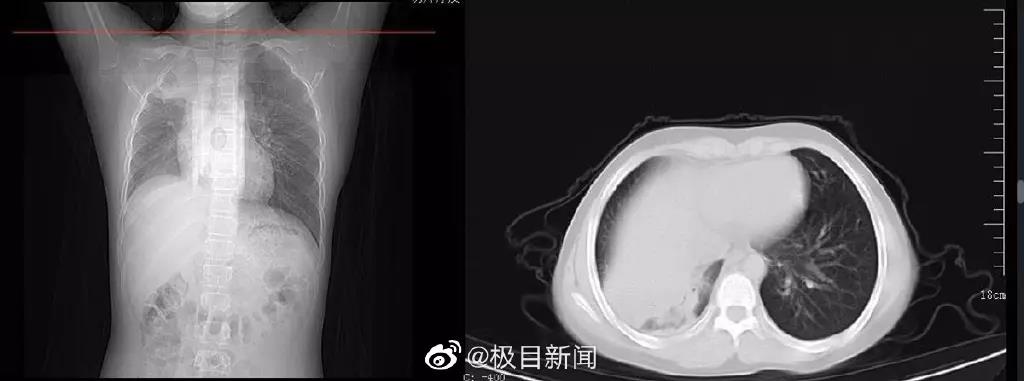

比如前几天,武汉有一位70多岁的吴婆婆,在感染之后,她没发烧、没咳嗽,所以家人们误以为老人是症状轻,没有过多在意。

但谁知,四五天,老人突然出现神志不清的症状。

急忙送进医院一看:缺氧非常严重,双肺已经白化!

这就是我们所说的——“沉默性缺氧”,又称“快乐性缺氧病”。

前两天,武汉就有一个仅12岁的男孩周周,查出了白肺。

原本一星期前就已经出现了症状,但是父母害怕医院病毒聚集会交叉感染,便决定在家治疗。

可是孩子烧退之后,咳嗽不但没有好转,还出了呕吐+胸闷的情况。

这时候才下定决定去医院检查,经初步判断孩子已经发展成肺炎,且肺部已经白了一大片了。